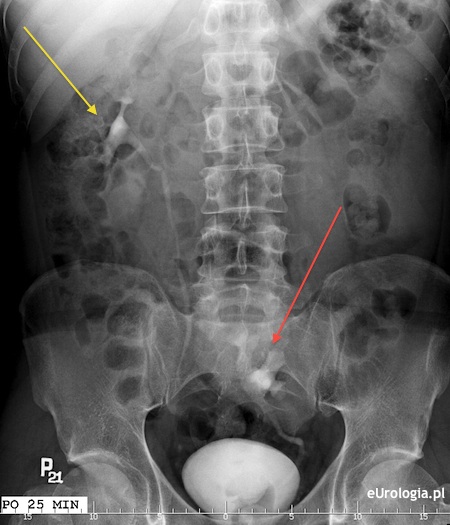

Fot. Ektopia miednicza lewej nerki - obraz urograficzny.